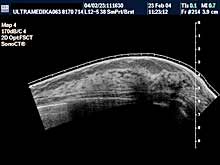

- Pregled podrazumeva pregled parenhima dojki

sa procenom limfnih žlezda i krvnih sudova,

- ako postoji promena i mikrokalcifikacija obavezna je primena: 3D Sono CT i 3D CPA i Broad

band-CD i CPD,

Tačna lokalizacija promene se vrši uz pomoć PANORAMA moda.